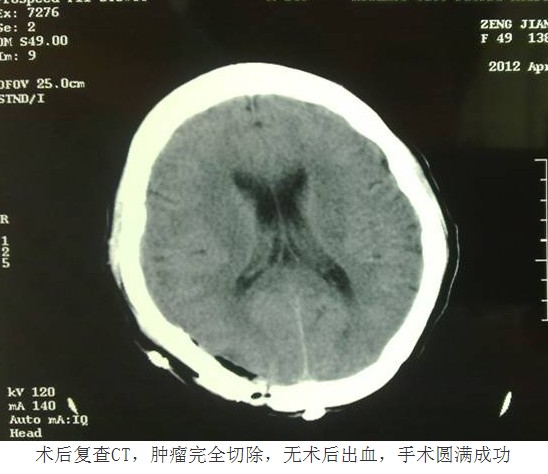

憑借先進(jìn)的技術(shù)與豐富的經(jīng)驗,換來的是患者快速的康復(fù)。由于手術(shù)核心部分均是在顯微鏡下操作,在完整切除腫瘤的同時,最大限度減少了對周圍正常腦組織的損傷,術(shù)中出血很少,因此術(shù)后患者沒有出現(xiàn)任何中樞感染、神經(jīng)功能障礙等異常情況,復(fù)查頭顱CT顯示腫瘤完整切除,無術(shù)后出血。術(shù)后第十天,患者即痊愈出院。